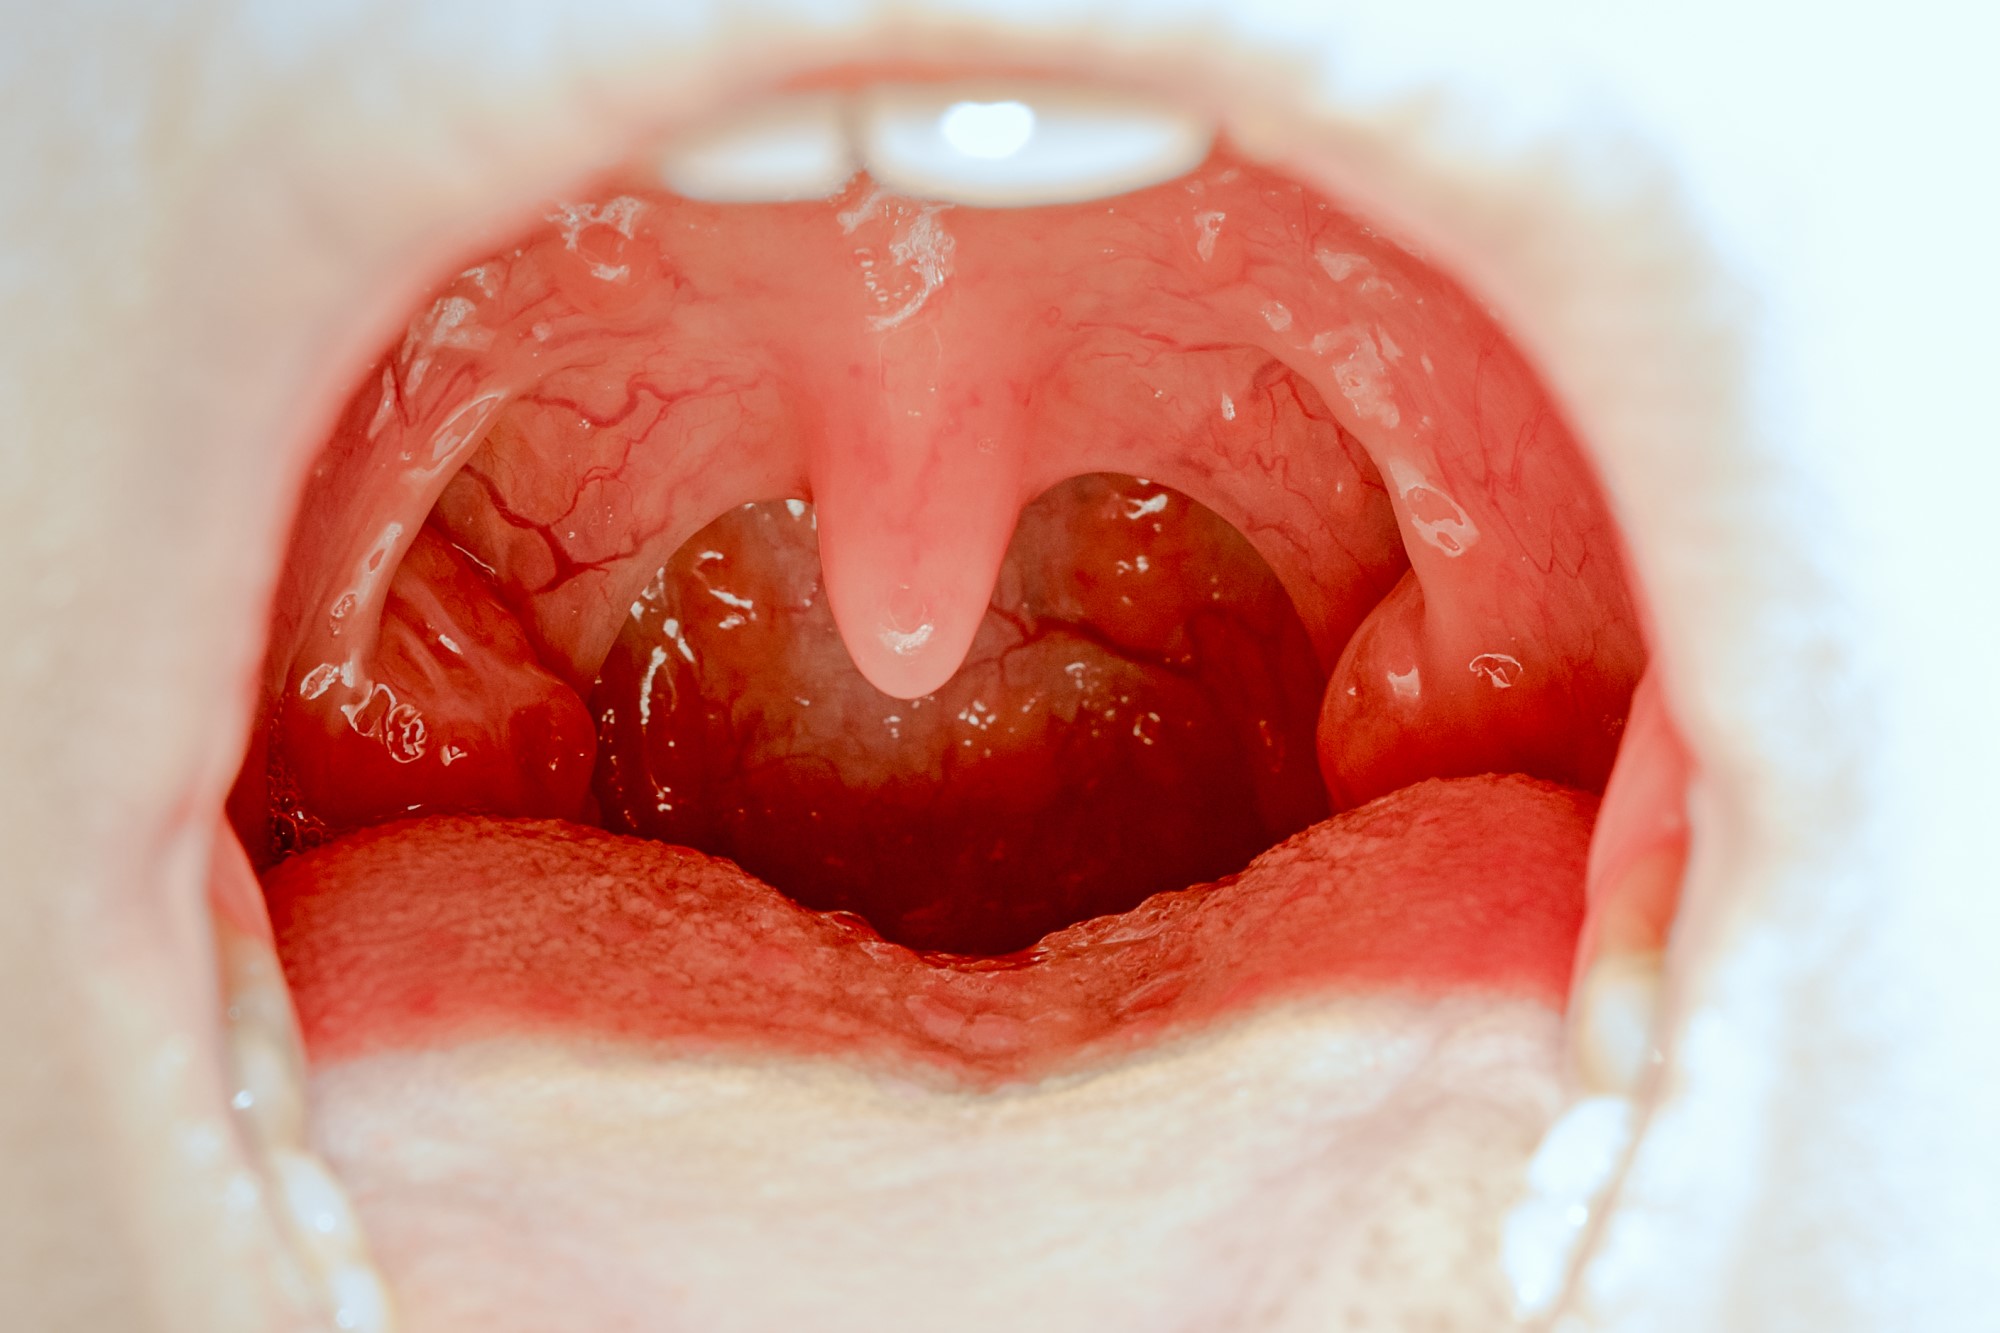

Радиоволновая тонзиллэктомия – способ удаления небных миндалин (гланд) с помощью их иссечения высокочастотными радиоволнами.

Показанием к удалению небных миндалин служит утрата ими способности выполнять свою функцию. Чаще всего это происходит при хроническом тонзиллите с обострениями до 4-5 раз в год, частых ангинах, паратонзиллярном абсцессе. Миндалины играют важную роль в иммунной системе человека, поэтому снижение/утрата их функциональности может привести к следующим состояниям:

Радиоволновую тонзиллэктомию часто назначают, когда необходимо удалить небные миндалины не целиком, а частично, сохранив при этом некоторое количество лимфоидной ткани.